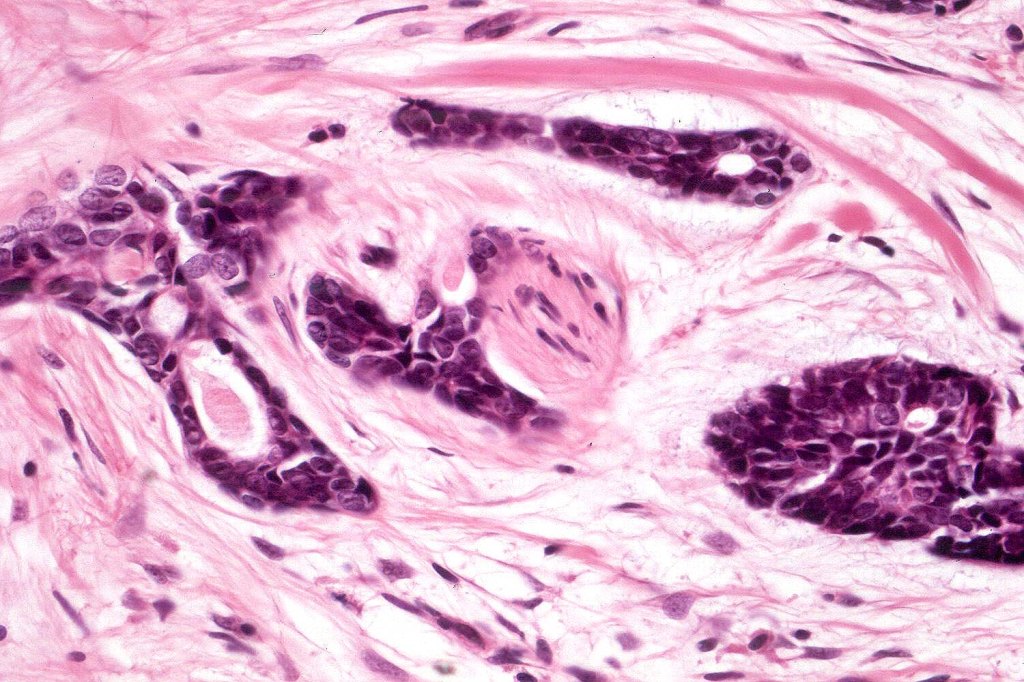

Histological features

•Biphasic tumor (myoepithelial & epithelial)

•Presence of myoepithelial cells

•Perineural infiltration*